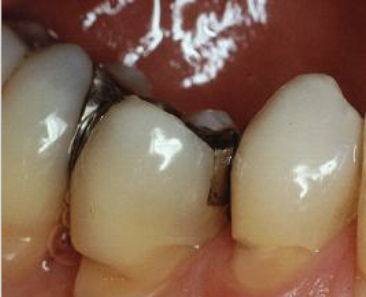

common in apical/ mid root; associated with cysts, tumors, ortho, excessive occlusal stress, reimplantation of avulsed tooth

external resorption

rare, injury to pulpal tissue (trauma)

internal resorption

internal resorption affecting crown

pink tooth of mummery